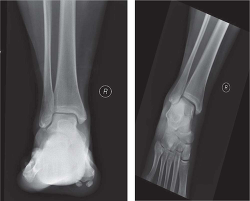

Radiographic evaluation included anteroposterior, lateral, and mortise with a gravity stress view of the ankle. This revealed an anterior process fracture of the calcaneus (see Figure 1) as well as widening of the medial clear space, consistent with ligamentous injury (see Figure 2). Given this, as well as noted ligamentous laxity on examination, a magnetic resonance imaging (MRI) of the ankle was obtained. The MRI revealed the known anterior process fracture without significant displacement, bone contusions throughout the midfoot, split tear of the peroneus brevis, and partial tear of the anterior talofibular ligament. These associated soft tissue findings are commonly reported with anterior process fractures (Ouellette, Salamipour, Thomas, & Kassarijian, 2013).

Figure 2 - Click to enlarge in new windowFigure 2. Note medial clear space widening on the gravity stress view (right).